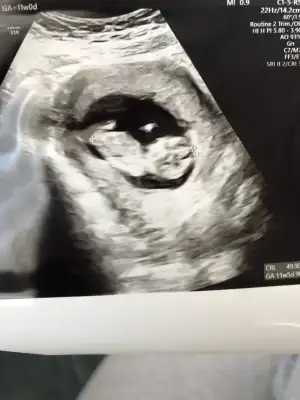

En iyi 11 12 13 haftalar olmalı şimdilik kız yönünde ama yanıltabilirIkra meyra bana da yorum yapar mısın cinsiyet için

burada 9 haftalıktı belli olur mu bilmiyorum o haftada ama bir bakabilirsen sevinirim

Öğrenince yazacağm mutlaka teşekkür ederimKız gibi sanki

YaaEn iyi 11 12 13 haftalar olmalı şimdilik kız yönünde ama yanıltabilir